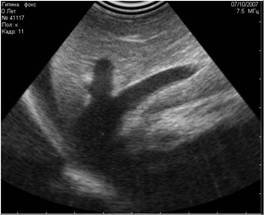

- эмфизема плода при беременности;

При пневмоперитонеуме артефакт реверберации проявляется как яркие лучи, идущие из-под диафрагмы при трансабдоминальном сканировании в дорсальном лежачем положении животного. Причиной пневмоперитонеума (3;5) могут быть:

Необходимо помнить о том, что артефакт реверберации говорит только о наличии пневмоперитонеума, а не о его источнике.

![]() |

Рис. 20. Артефакт реверберации. Яркие гиперэхогенные точки - это пузырьки газа. Гипоэхогенные полосы под ними - это реверберация. |

Рис. 21. Артефакт реверберации от газа в желудке. |